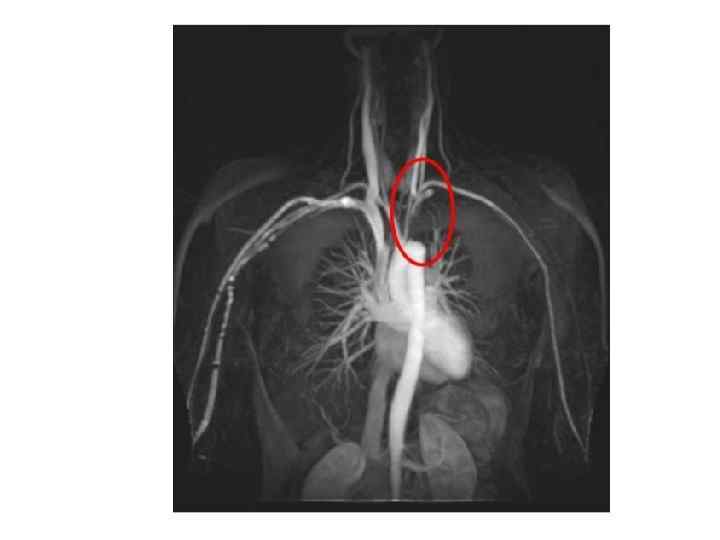

Инструментальные методы обследования • • ЭКГ, Эхо. КГ - гипертрофия левого желудочка, обусловленная артериальной гипертензией Диагноз коарктации аорты окончательно устанавливается с помощью аортографии!!!

Резкая коарктация аорты в типичном месте, просвет сосуда < 1 мм (фронтальная проекция) Ангиография после постановки эндопротеза во фронтальной проекции, просвет сосуда увеличен до 23 мм